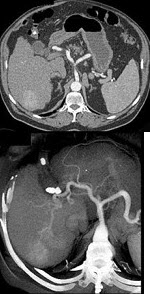

男,44岁,患乙肝多年,现腹痛,腹胀,AFP增高,消瘦、乏力,影像检查如图,最可能诊断是( )

A:肝血管瘤

B:肝腺瘤

C:肝转移瘤

D:肝硬化、肝癌

E:肝结节性增生